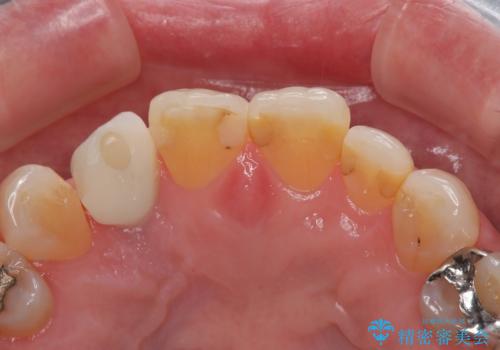

- 前歯のインプラント治療を検討して様々医院を探していたところ、1回の手術で治療ができるとのことで来院された患者様です。

長期間の治療と外科処置の回数が多くなることを懸念して、なかなかインプラント治療に乗り出せなかったそうですが、1DAYインプラントというものがあることを知り、当院にいらっしゃいました。

仮歯を事前に用意し、インプラント埋入時に即日で仮歯を装着する、即時荷重インプラントの計画で治療を進めて行くこととしました。

来院間隔があいたため、予定よりも長くなりましたが、大きなトラブルもなく、外科処置は1回のみ、最小の来院数で無事に治療を終えることができました。